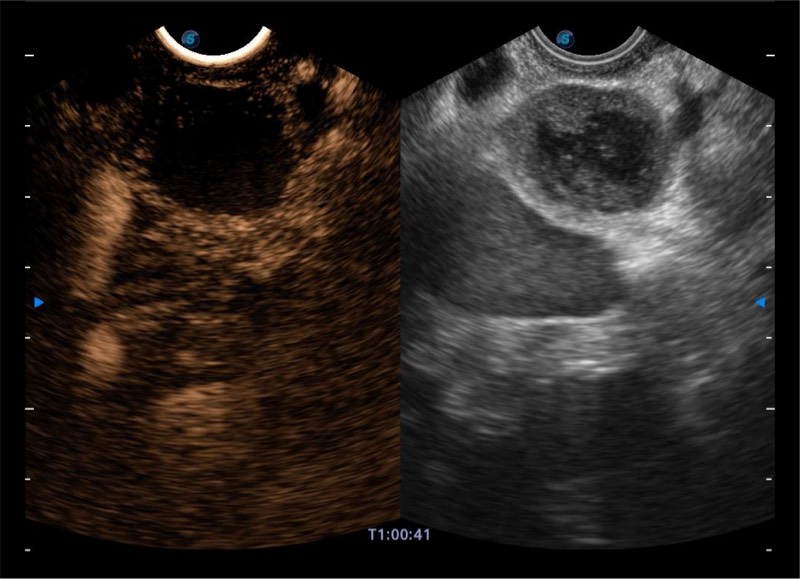

搭载百万级CMOS成像技术

及自主研发凸阵换能器,

可呈现优质的内镜和超声画面

基于二十年的超声技术积累,九州酷游提供了最新一代的独立超声主机,在提供高质量图像的同时满足多学科使用。具备常见多普勒技术并提供弹性成像、声学造影等高端影像技术。新一代传感器具有更强的抗干扰能力并减少图像伪影。

4-12MHZ宽频输出